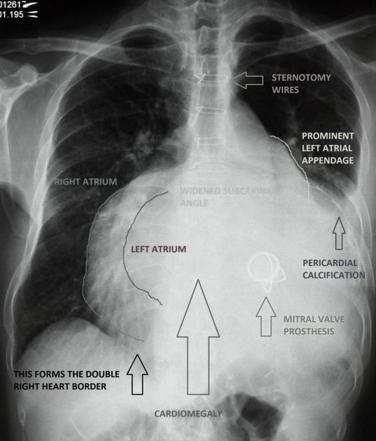

Mitral stenosis investigations CXR?

left atrial enlargement, cardiac enlargement, pulmonary congestion, mitral valve calcification.